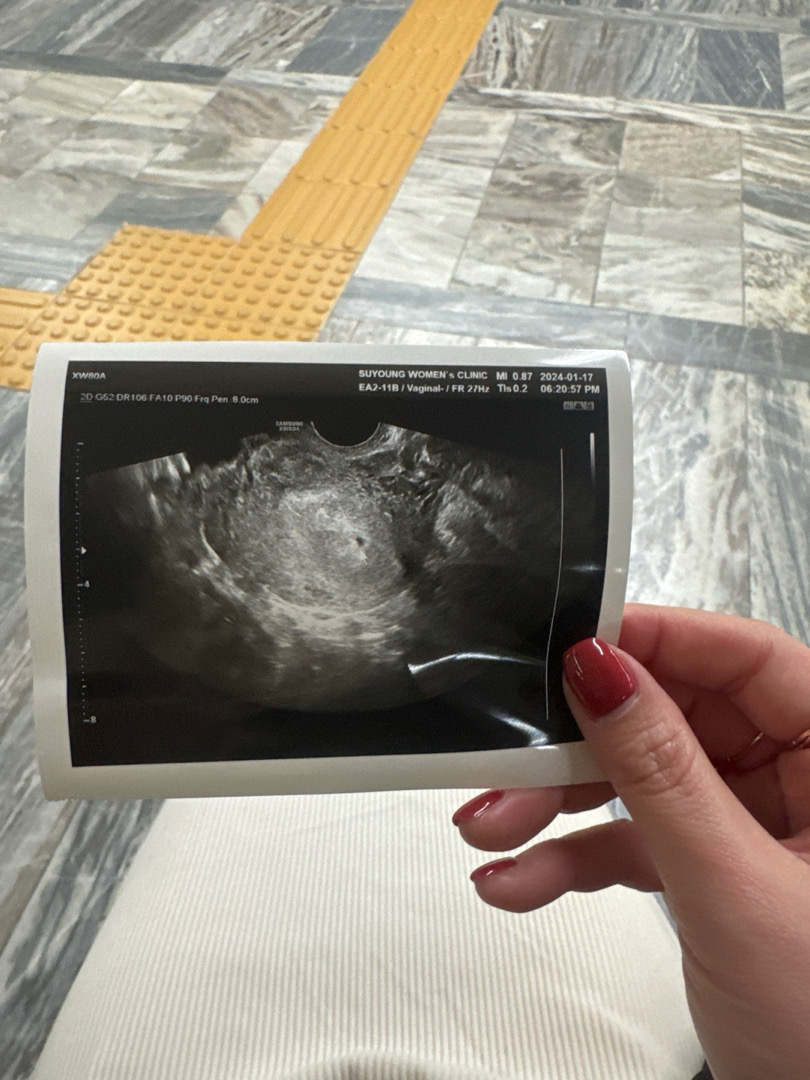

마지막생리시작일 12/13일 12/27일 배란예정일이었고 생리 규칙적이여서 1/17일 5주차0 일 되자마자 애기집 보일거같다고 다들 말해주셔서 다녀왔는데 너무작다고 이게 맞는지 아닌지 모르겠다고 여성의원에서 말하더라구요 피검사나 이런건 안했구요! 산부인과를 가야할까요..?! 의원이랑 진료가 다른가요? 친구가 원래 극초기면 피검사하는데 왜 안했냐고 해서 의원이랑 다른가해서 여쭤봐용